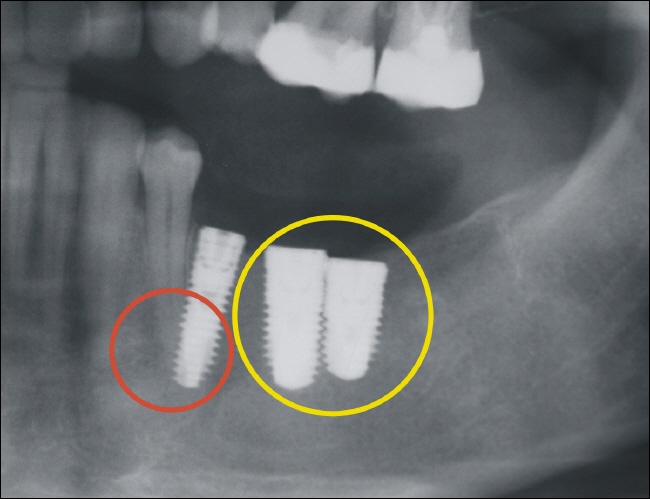

Perforationen ( oder das „Durchbohren“ des Knochens) sind die Folge einer fehlerhaften Ausrichtung der Implantatbohrung, oder aber die Folge eines Knochendefizits. Dabei besteht prinzipiell das Risiko der Verletzung von anatomischen Strukturen wie Blutgefäßen oder aber Nervenästen.

Wichtig ist, dass das Implantat circulär, also ringsherum von Knochen umgeben ist. Bei unzureichender Planung und Diagnostik steigt das Risiko von Perforationen.